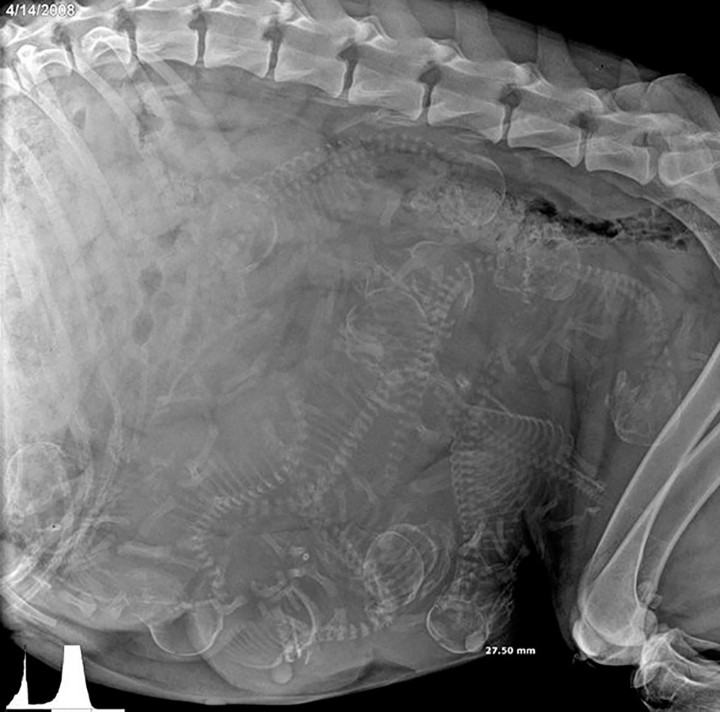

| Rentgen_tehotne_fenky.jpg (MildaX_) (28.3.2023 6:28) | ||

má naštěkáno v boudě  |

| Rentgen_tehotne_fenky.jpg (Ellen Ripley) (28.3.2023 6:05) | ||

| I say we take off and nuke the entire site from orbit | ||

| Rentgen_tehotne_fenky.jpg (S) (28.3.2023 0:33) | ||

| 10x ? | ||